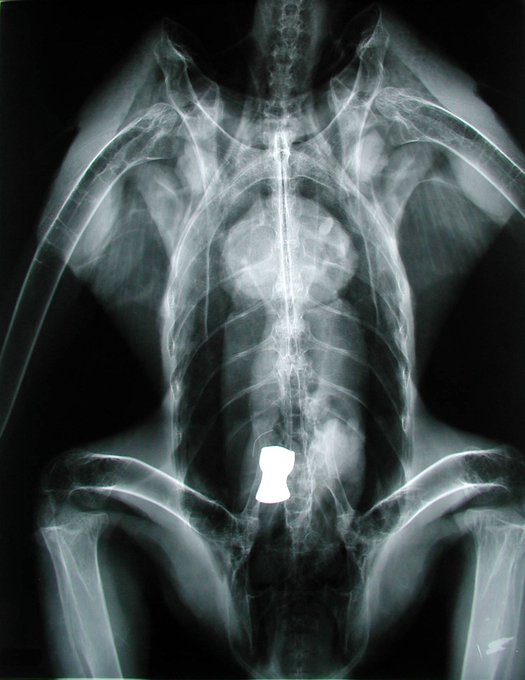

狩猟後に放置されたエゾシカの死体(狩猟残滓)を食べ、肉とともに鉛弾を飲み込んで鉛中毒死したオオワシ2症例。

① 1番目と2番目の写真は、鉛ライフル弾を摂食した個体のレントゲン写真と摘出した鉛弾。

② 3番目と4番目は散弾銃(ハーフライフル)用サボット弾(スラッグ弾)を飲み込んだ症例。